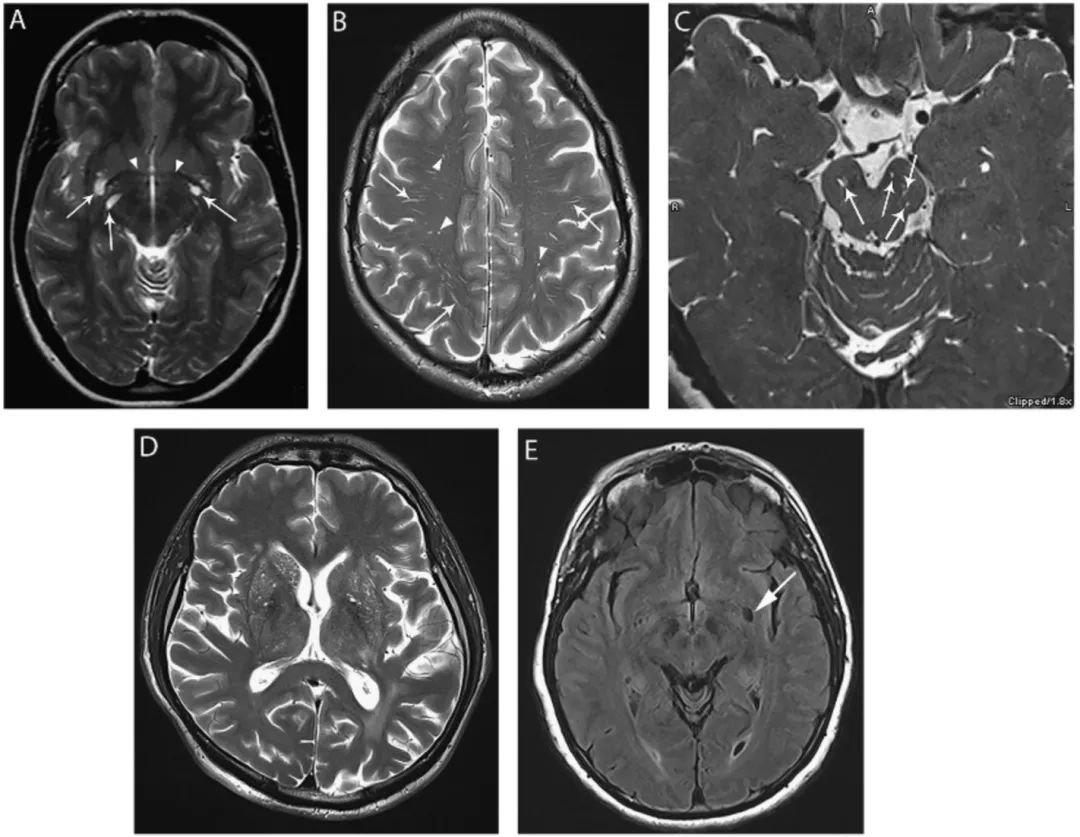

图2 血管周围间隙(PVS)

(A) I型,前连合(楔形箭头)水平双侧大小不同的血管周围间隙(箭头);(B)II型,双侧半卵圆中心高信号的血管周围间隙 (箭头);(C)III型,中脑被盖-脑桥边界的高强度血管周围间隙(箭头);(D)T2WI像可见双侧基底节区血管周围空间弥漫性扩张,(E)FLAIR像显示左侧基底节区有一个扩大的PVS(箭头),周围无T2高信号。